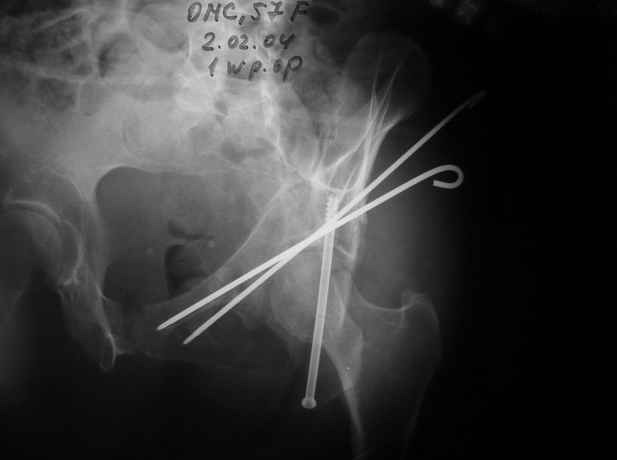

Не дождавшись советов, в понедельник прооперировал больного, заняло времени..., но все сделал в один этап: сначала фиксировал ипсилатеральный перелом бедра и шейки реконструктивным гвоздем Smith&Nephews, потом из расширенного илеофеморального доступа фиксировал перелом крыла подвздошной кости тягловым винтом, нейтрализующей пластиной заднюю колонну, и тягловыми винтами 3,5 мм переднюю колонну.

Несмотря на расширенный доступ, особой кровопотери не было, перелил только одну дозу эр.массы и на утро Нв- 10.5 и как ни странно больной не жалуется на сильные боли и стопа не *висит*, хотя при интраоперационной ревизии седалищного нерва обширная гематома в периневральной оболочке.

К сожалению, набора для ретроградного или антеградного реконструктивного штифтования в операционной нет, поэтому доставка заняла н-ное время. Вопрос, который возник у меня- по поводу оптимальной тактики хирургии: вся фиксация в один этап из расширенного доступа или последовательно сначала бедро и позже реконструкция впадины, комбинированный доступ к впадине отдельно к передней и задней колоннам или из расширенного илеофеморального одного доступа. Все-таки решил остановиться на одноэтапном подходе и спустя 5 дней (как раз и наборы привезли) из расширенного илеофеморального доступа сначала фиксировал реконструктивным штифтом Smith&Nephews бедро и

шейку (благо перелом шейки 2 типа -относительно стабильный) затем фрагмент крыла подвздошной кости Lag screw, далее пластина на заднюю колонну и винты в переднюю колонну.(с размерами и направлением винтов ошибка вышла:-((, но интраоперационно у меня была полная уверенность , что винты *ушли* в лонную кость).

Еще раз спасибо за комментарии и готовность помочь с имплантами. Постоп картинки в приложении,